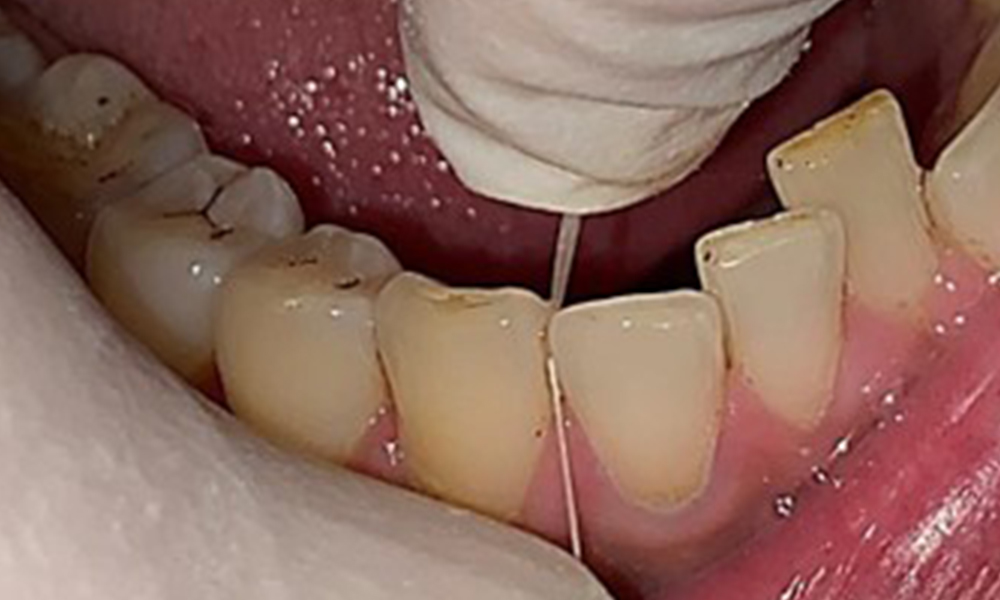

The patient has full dentition with a total of 28 teeth. There were noteworthy erosions and attritions. (Fig. 4, Fig. 5). Due to bruxism, the patient has been wearing a splint with an adjusted bite block at night for many years. The erosions were caused by long-term consumption of isotonic beverages. No periodontal bone loss or active caries were observed.

Close-up view of teeth

Fig. 5: Close-up view of teeth 45 to 47. The green arrows show dental attrition and erosions of the buccal cusps with partial enamel loss, © Dr R. Krapf

Full complement of adult teeth with no caries or radiologically recognizable bone loss was observed (Fig. 6). Radiological enamel and cusp loss were particularly evident on 36 and 37.